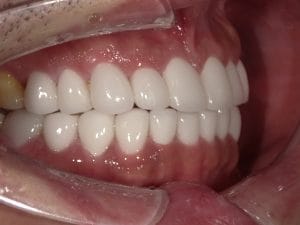

Case033

前歯が虫歯なのと、保険のプラスチックで大きく治療されていて色が悪いこと、歯並びが出っ歯気味であることを気にしてセラミックにしたいという主訴で来院された患者様です。

虫歯が大きかったところは神経治療をきちんと行い、

初診時を含めてトータル4回のご来院で完了です。

今回は前歯を下げる、歯列を整える、白すぎず自然に綺麗に見える色というご希望に沿って治療しました。

ご興味のある方はいつでもご相談ください。

担当 理事長 佐藤 悠野